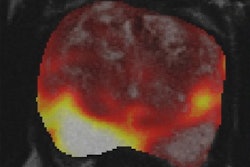

And lastly, Swiss and German researchers have obtained promising results with a novel PET imaging agent that could help guide and assess treatment for people with various neurological diseases. In a preclinical study, the agent targets receptors in nerve cells in the brain that are involved in learning and memory, and it could be useful for studying conditions such as Alzheimer's and Parkinson's diseases, as well as multiple sclerosis.